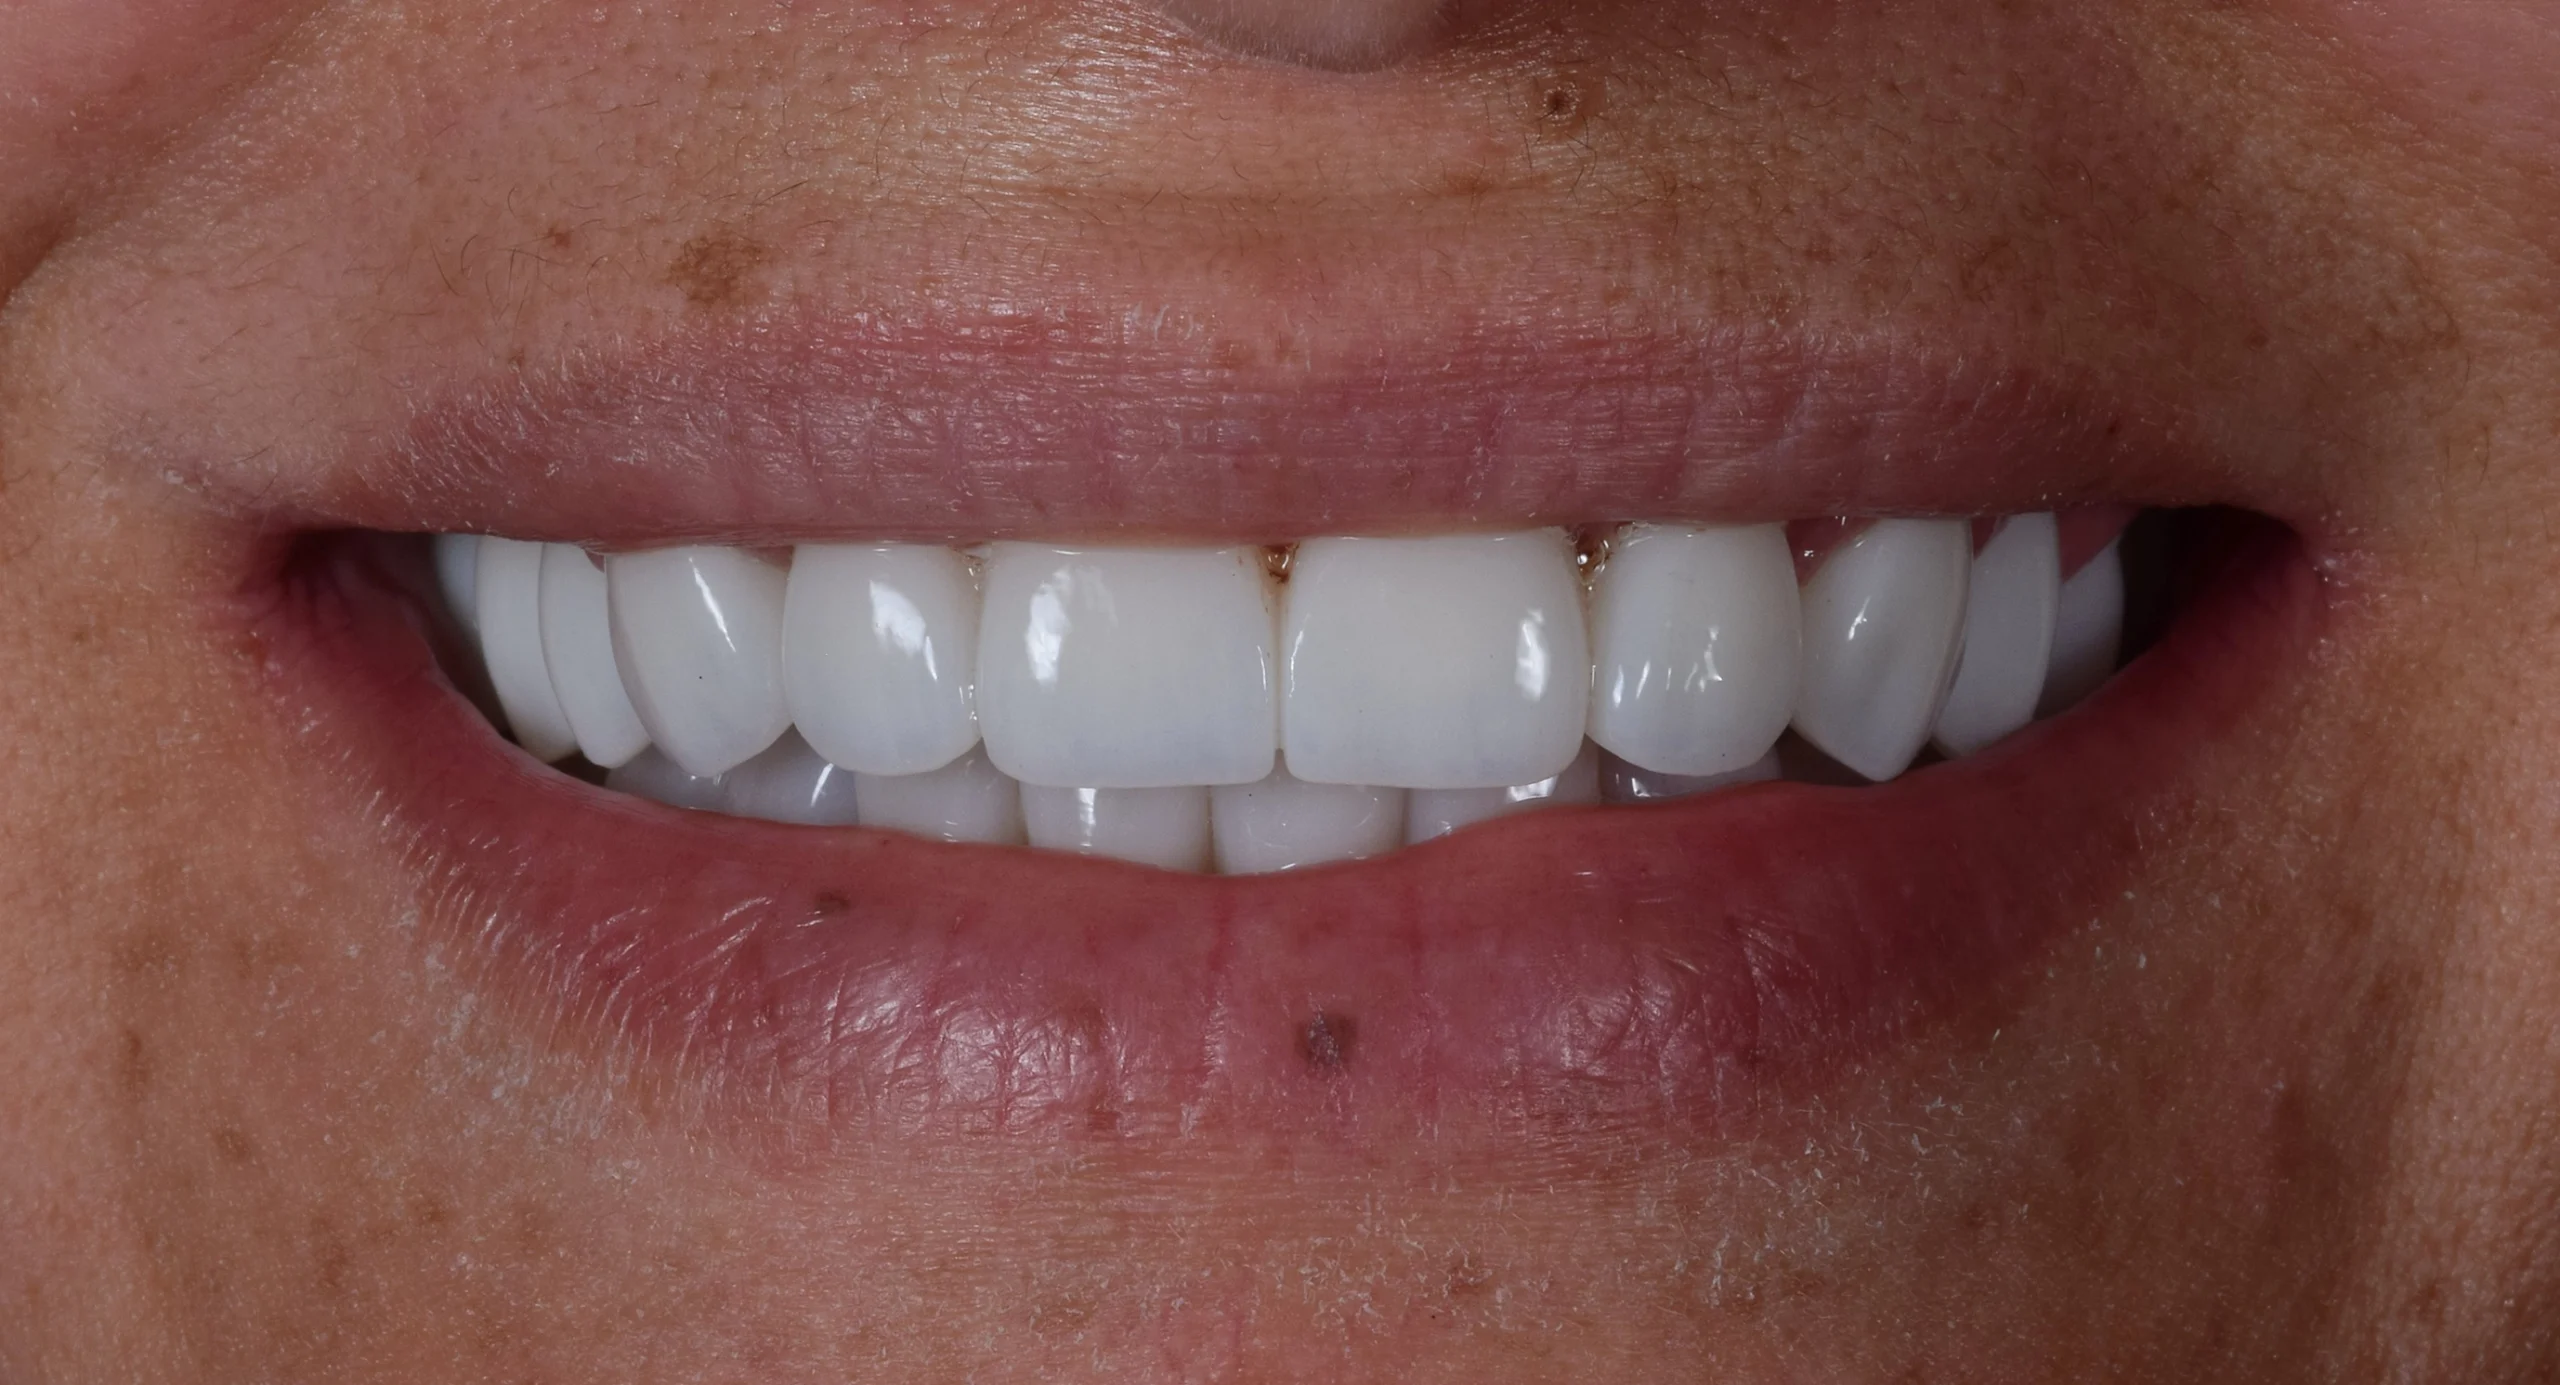

In the first phase, we placed six dental implants using computer-aided surgical guides. This technology allowed us to achieve exceptional precision, ensuring optimal positioning, stability, and long-term success of each implant.

Following a healing period of 4 months, during which complete osseointegration occurred, we moved to the next stage. The patient was fitted with a prototype “try-on” smile, giving her the opportunity to preview the final result and ensure complete satisfaction with the shape, size, and appearance.

After a short additional healing period of 2 weeks, we delivered the final restorations—high-quality zirconia crowns and bridges. The result is a natural-looking, durable, and radiant smile that perfectly complements her facial features.

Today, she feels more confident than ever before. She can smile, speak, and eat freely again—and most importantly, she is proud to show her new, healthy, and beautiful Hollywood smile.Â